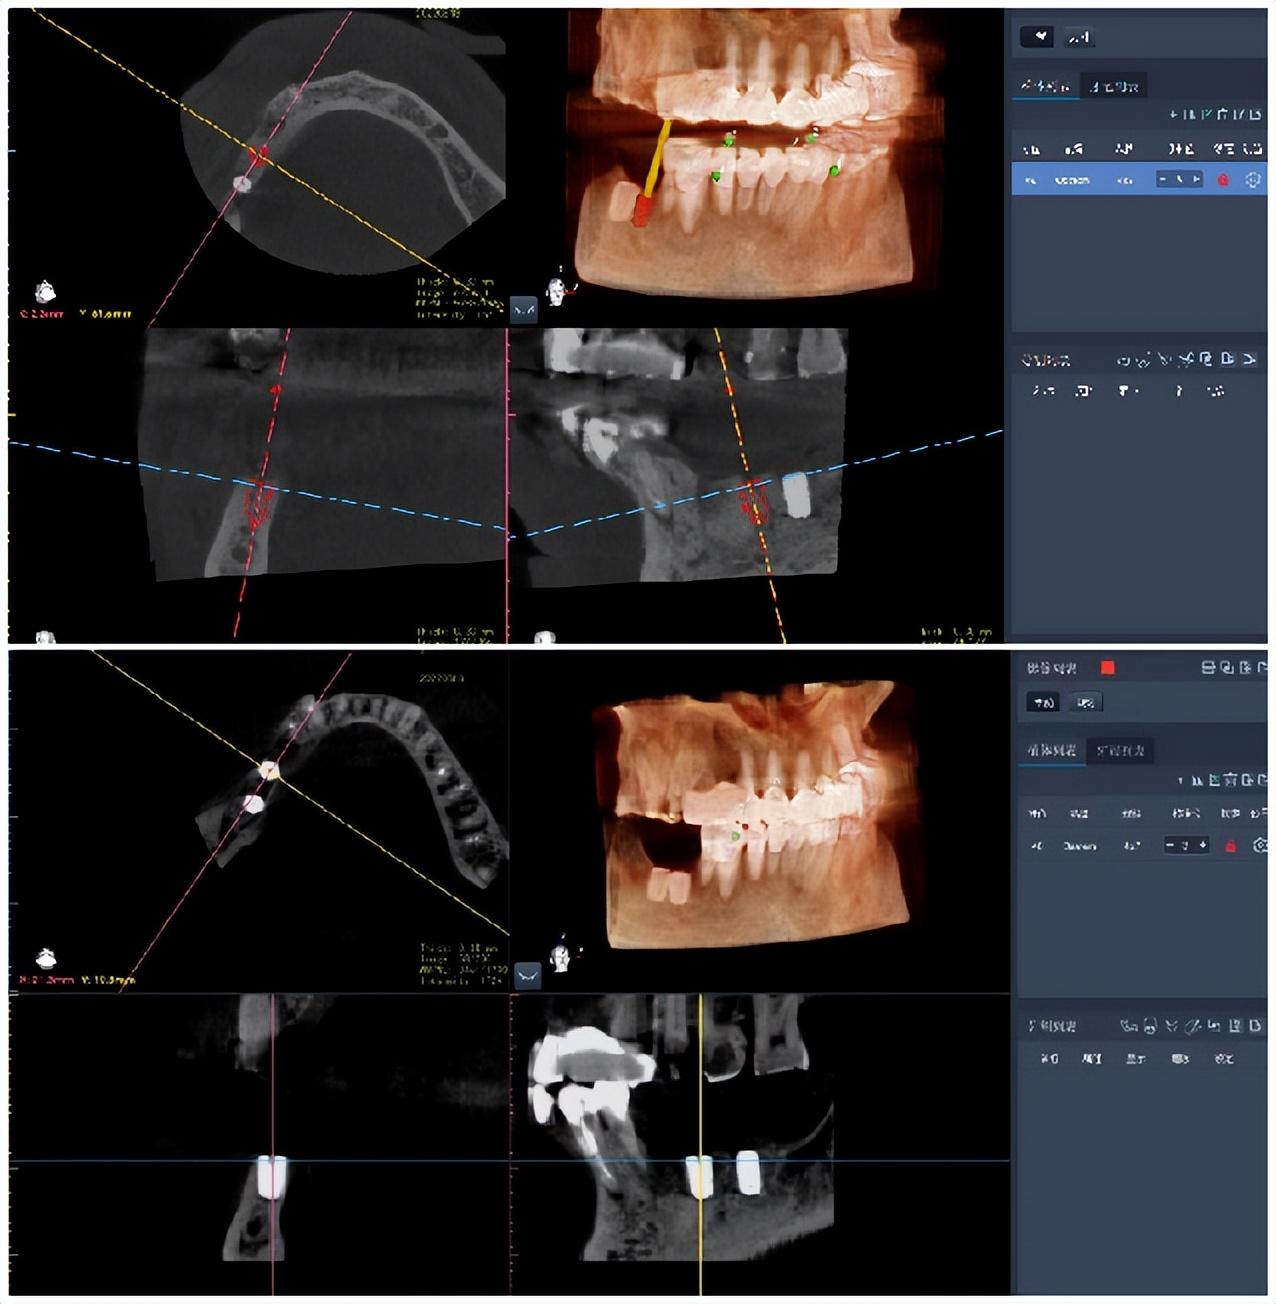

在家人的勸說下,備受折磨的陳大哥輾轉(zhuǎn)來到哈爾濱醫(yī)科大學附屬口腔醫(yī)學院口腔修復(fù)科尋求幫助,科室副主任劉鑫教授首先詳細了解了他的病史及功能訴求,通過綜合研判,決定采用數(shù)字化技術(shù)手段,為患者訂制個性化種植方案。劉鑫主任團隊先后采集患者全口錐形束CT影像數(shù)據(jù)、數(shù)字化口腔印模掃描數(shù)據(jù),并導入數(shù)字化手術(shù)設(shè)計軟件進行分析,發(fā)現(xiàn)患者右下后牙46、47牙槽嵴平均寬度5.2毫米、牙槽嵴頂至下頜神經(jīng)管的距離平均值為8.5毫米。

后,在綜合研判的前提下,為有降低手術(shù)意外,規(guī)避下頜神經(jīng)管被誤傷,以及考量陳大哥年齡身體條件等各方面因素,劉鑫主任本著、微創(chuàng)原則,決定采用國產(chǎn)種植機器人加持的無切口、無翻瓣的手術(shù)術(shù)式,以減少出血和手術(shù)創(chuàng)傷,改良預(yù)后,提高術(shù)后種植體的佳植入角度及方向、包括冠上修復(fù)體的佳修復(fù)設(shè)計方案,使患者獲益大化。

手術(shù)后的第一時間,陳大哥給劉鑫教授團隊點了個贊:“真的很神奇,機器人手臂對我的操作一點感覺都沒有,我滿意!”那種術(shù)前的焦慮、恐懼的心緒早已煙消云散。根據(jù)術(shù)前口腔手術(shù)機器人設(shè)計方案的植入位點與術(shù)后實際植入口腔種植體位點的三維數(shù)據(jù)對比,劉鑫教授通過精細測量發(fā)現(xiàn)種植前后的種植體位置數(shù)據(jù)誤差值不足0.4毫米,了手術(shù)過程、微創(chuàng)、。

而與傳統(tǒng)“自由手”種植手術(shù)相比較,口腔手術(shù)機器人可通過術(shù)前可視化體外模擬,術(shù)中定位、動態(tài)導航、人機隨動等功能,極大地增強了種植術(shù)的精度和質(zhì)量,縮短手術(shù)時間,進而達到標準化種植的目的。不僅如此,機器人種植手術(shù)還能夠提供可視化的術(shù)前規(guī)劃方案,通過手術(shù)設(shè)計,幫助術(shù)者提前預(yù)測調(diào)節(jié)難度并規(guī)避手術(shù)風險,使調(diào)節(jié)過程和術(shù)后結(jié)果更具有可預(yù)期性,讓患者的手術(shù)過程及種植體位置從“了然于心”到“歷歷在目”。劉鑫教授緊緊把握這些新業(yè)態(tài),不斷開拓創(chuàng)新,迄今已在臨床開展了上百例數(shù)字化口腔種植手術(shù),證實其在臨床手術(shù)中應(yīng)用展現(xiàn)的優(yōu)勢遠超以往。